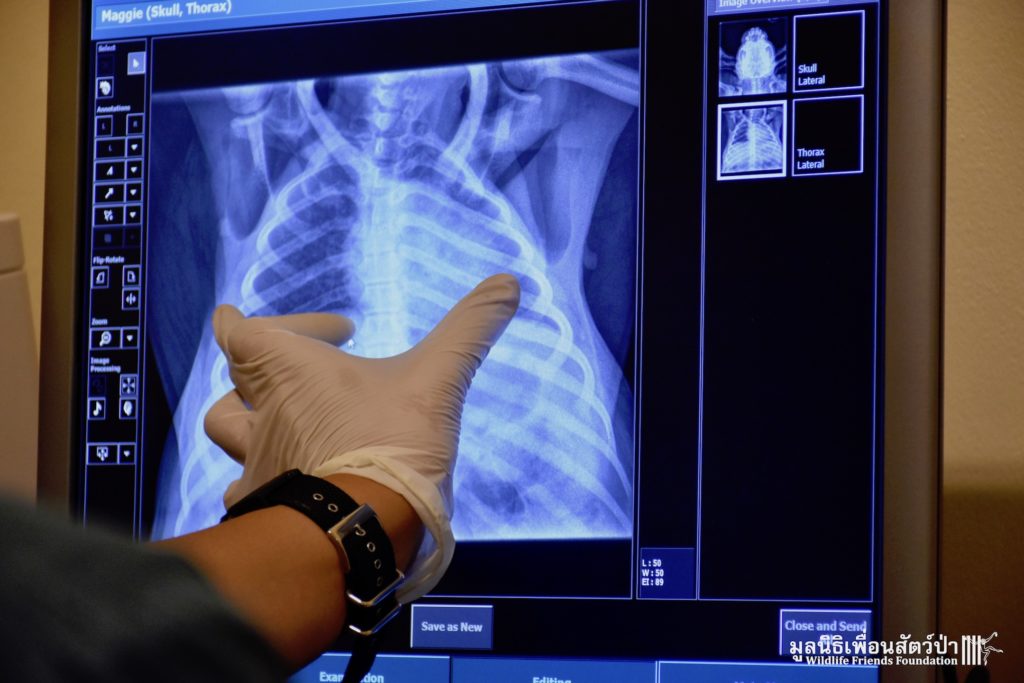

WFFT’s resident great apes, Maggie and Chico the critically endangered orangutans, are now much closer to their wonderful new home. We have moved them from their old night enclosure to a new side enclosure connected to the new huge open forest area we have created for them. During the move they made a pit stop at the WFFT Wildlife Hospital so a full health check could be performed, including a full body x-ray which was performed for the first time. This whole operation would have not been possible without the kindness and support of Mr. Mike Beets, so thank you Mike!!! And a great big thank you to the International Primate Protection League. All the team at WFFT are waiting in excitement to see these very special apes out exploring very soon. Watch this space over the coming days for an update about their first exploration expedition around their new home.